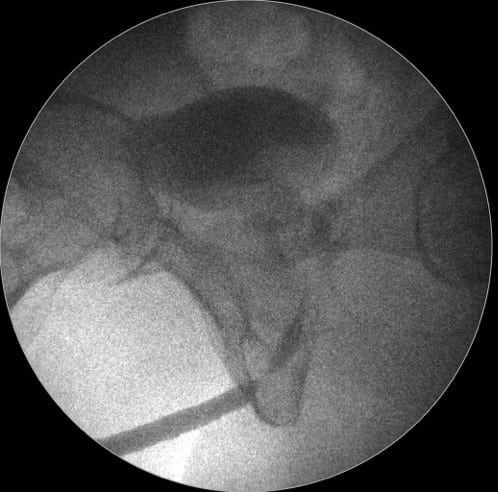

Dr. Marcel Rad – Când evaluăm strictura de uretră ce vedem? Vedem un canal, vedem în uretrografie o zonă de gâtuire, de stenozare a canalului, dar nu vedem şi nu putem să ne dăm seama, indiferent de cât ne chinuim să evaluăm cu ecografie, cu RMN, nu putem să evaluăm corect zona de fibroză, zona de ţesut cicatricial.